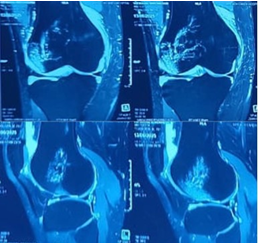

The patient was administered painkillers and ice fomentation and underwent an X-ray of his knee joint. An osteochondral fragment was visible in the knee joint, but we were not able to determine where the origin of the fragment was. A computed tomography scan of the knee joint was performed, and the fragment was identified to be originating from the distal LFC and was measuring 2.5 cm × 2.5 cm. The Insall Salvati ratio was 1.36, and the Caton Deschamps Ratio was 1.6. The Tibial Tuberosity–Trocheal Groove (TT–TG) distance was 20 mm, and his knee was a Dejour type B. A standing scannogram was not possible for the patient due to pain. The decision to avoid a tuberosity osteotomy was made as the TT-TG distance was just at the borderline with a slightly high Caton–Deschamps index. The decision to perform a lateral parapatellar arthrotomy with a strong medial patellofemoral ligament (MPFL) reconstruction was deemed sufficient to maintain patella stability. The final decision would be taken intraoperatively after tightening of the MPFL graft regarding the requirement of a tuberosity osteotomy. Fig. 2, 3.

Figure 2: Computed tomography scan of right knee – axial cuts.

Figure 3: Computed tomography scan of right knee – coronal and sagittal cuts.